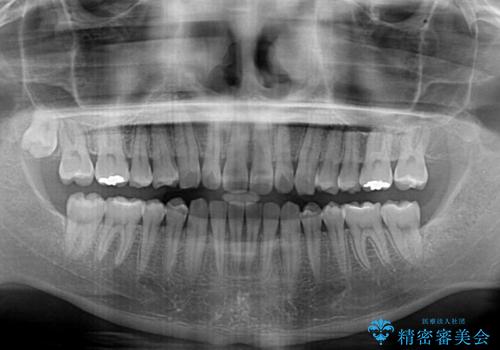

- 上下前歯のデコボコを気にして来院された患者様です。

以前矯正をした後戻りということで、歯列不正はそれほど大きくなかったため、インビザライン・ライトを用いて矯正治療を行うこととしました。

1日22時間以上しっかりと装着してくださったので、半年かからずに治療を終えることができました。